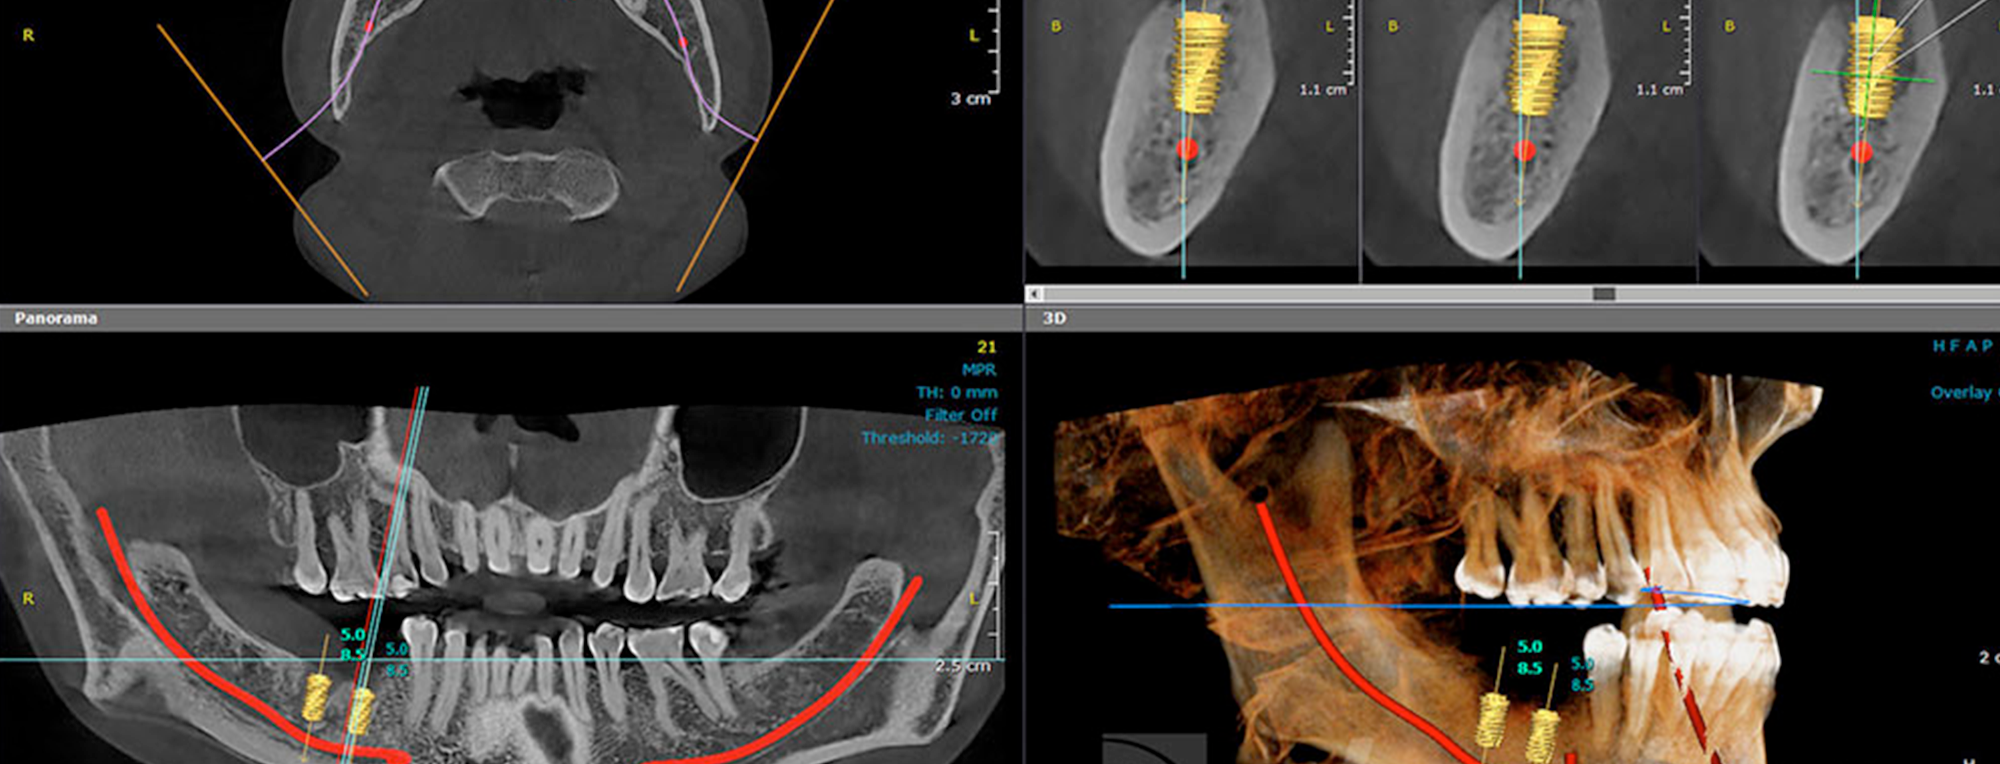

A diferencia de la radiografía panorámica, la Tomografía Computarizada (TAC) genera imágenes tridimensionales. Esto permite una visión detallada y precisa de las estructuras óseas, tejidos blandos, y vías nerviosas, algo crucial para planificar procedimientos complejos como ortodoncia, implantes o endodoncias.

En MF Dental Center, nos tomamos muy en serio la precisión en el diagnóstico. Por eso, utilizamos la Tomografía TAC como complemento indispensable a las radiografías panorámicas para ofrecerte el tratamiento más seguro y efectivo.